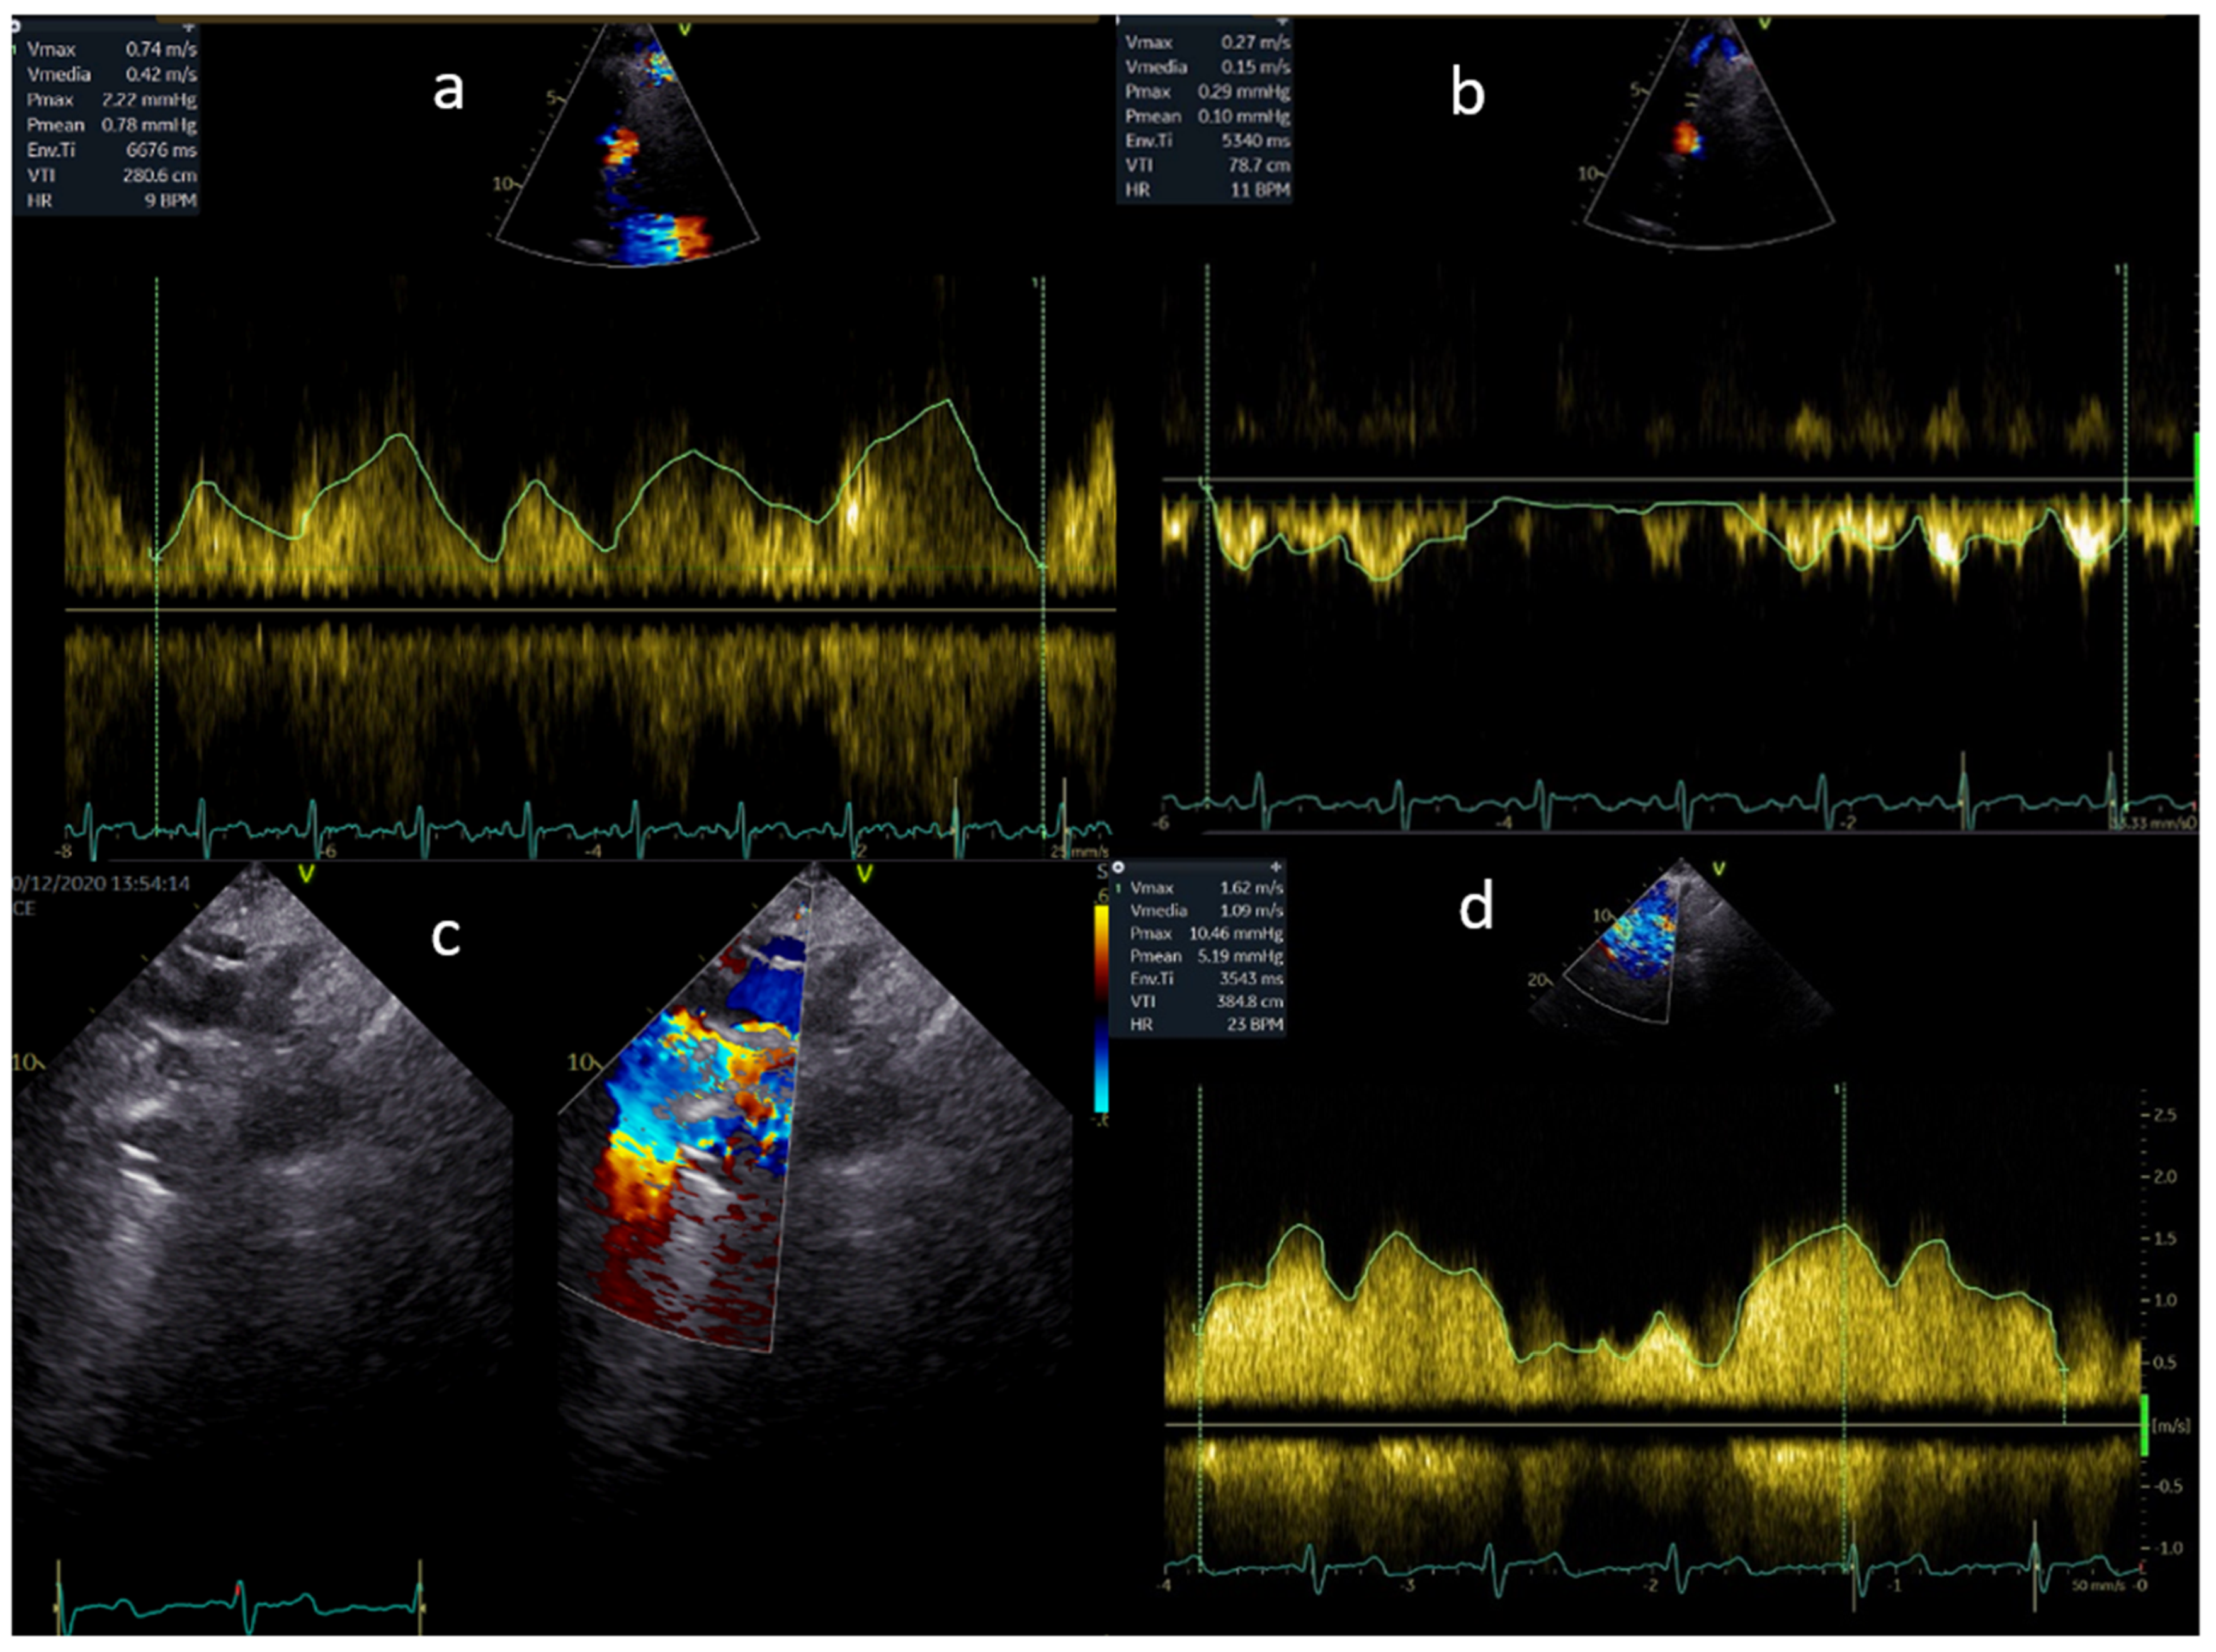

Ventricle function assessment by echocardiography is shown in Figure 1.

Figure 1. Ventricle function is assessed in a, b, c and d by AV S/D, 3D EF, LS, and FAC, respectively.